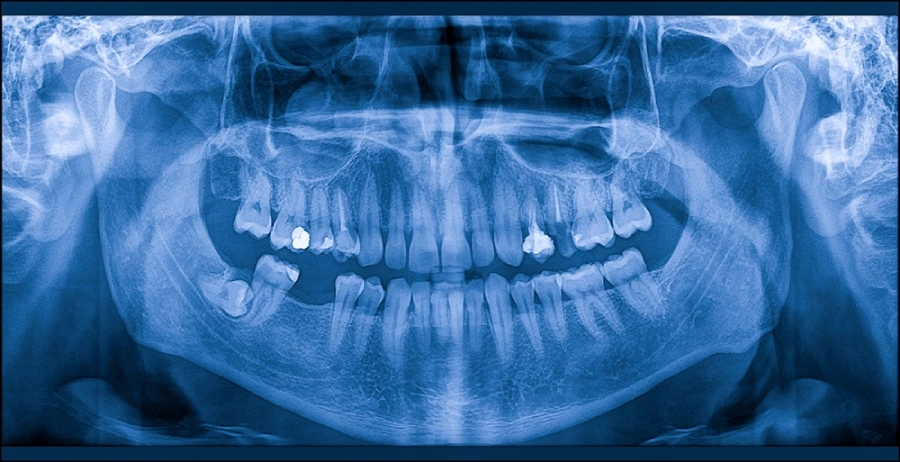

AI Analysis Example

Example of AI-generated diagnostic report with annotated imaging

AI Annotated Dental X-Ray

Caries - #14

Bone Loss - 4.2mm

Periapical - #3

AI-generated annotations highlight areas requiring attention with precise bounding boxes

AI Diagnostic Summary

#14 High Priority

Deep carious lesion detected on distal surface. Recommend immediate restoration.

#3 High Priority

Periapical radiolucency present. Endodontic evaluation recommended.

Posterior Region Monitor

Mild horizontal bone loss (4.2mm). Monitor periodontal health.